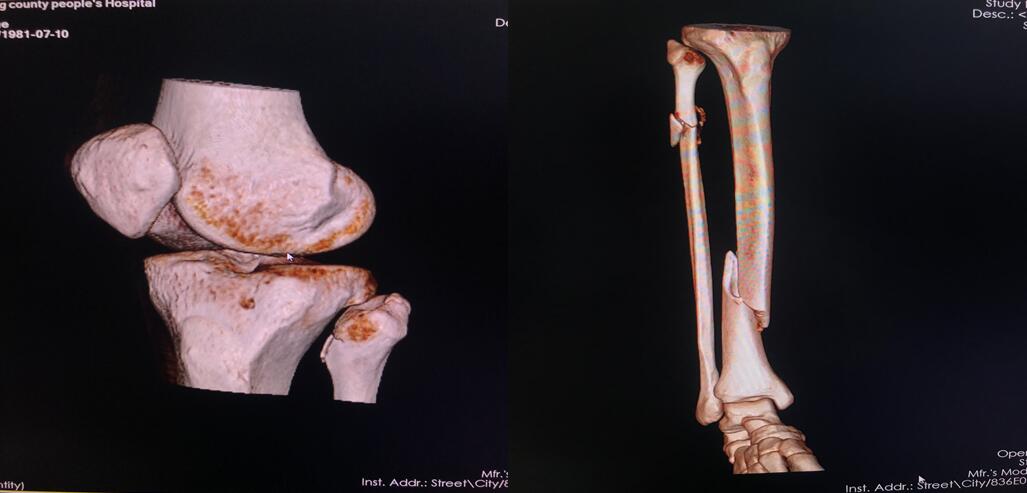

四、开展项目:科室现常规开展全身各部位CT平扫及增强检查、CT三维重建、CT血管造影(CTA、CTV)、(包括冠状动脉CTA)、CT尿路造影(CTU)、全身各部位DR摄片检查、床边摄片、同时开展胆系T管造影、CT定位下穿刺活检。

全身部位三维重建

全身骨三维重建